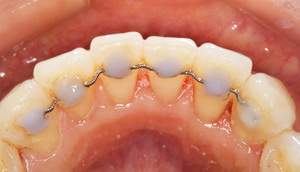

歯石除去、着色除去

治療前

治療後

| 年齢 | 25歳・女性 |

| 主訴 | 主訴:歯石除去、着色除去 治療部位:全顎 |

| 治療内容 | 初診検査・歯石除去・PMTC |

| 治療期間 | 60分 |

| 費用 | 合計約10,500円 初診検査約3,000〜4,000円 歯石除去約1,000円 PMTC5,500円(自費診療) (2024年6月現在) (歯の本数や検査内容で料金が変動します。) |

| リスク・副作用 | ・歯ぐきの炎症がある場合は歯石除去中に出血を伴う可能性があります。 ・処置後、知覚過敏が起こる可能性があります。 ・歯ぐきの炎症が治ると、歯ぐきが引き締まる為歯が長くなったと感じる事があります。 ・PMTCは歯を白くするものではなく着色・バイオフィルムの除去を目的としています。 |

| 治療方針 | 全顎的な歯石除去後、PMTCで着色とバイオフィルムを除去。 |

| 特記事項 | 矯正経験あり ホワイトニング経験あり |

| 担当者所見 | 歯石除去と前歯部の着色除去希望で来院されました。 下顎前歯の歯間部の歯石に対してフロス指導を行いました。 PMTCにより着色がなくなり、歯のトーンアップも感じられたと喜んでくださいました。 |